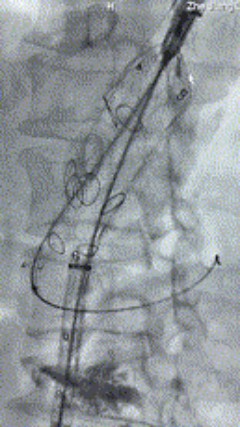

5. 撤出腹腔干导丝导管,经左肱动脉长鞘继续抓捕预置导丝将长鞘超选至另一侧内分支,后超选进肠系膜上动脉,沿导丝送入J9集团国际覆膜支架10*100mm一枚,近端重叠内分支,远端重叠于肠系膜上动脉,并予以10mm球囊后扩,手推造影显影良好。

6. 解除束径,打开近端后释放,经肱动脉长鞘超选支架外分支,并进一步超选右侧肾动脉,交换加硬导丝,送入覆膜支架6*50mm和7*60mm各一枚,并予以球囊后扩张,手推造影显影良好。

7. 经长鞘重新选入左侧外分支,并超选进左肾动脉,沿导丝送入外周血管覆膜支架7*60mm一枚,并予以球囊后扩张,手推造影显影良好。